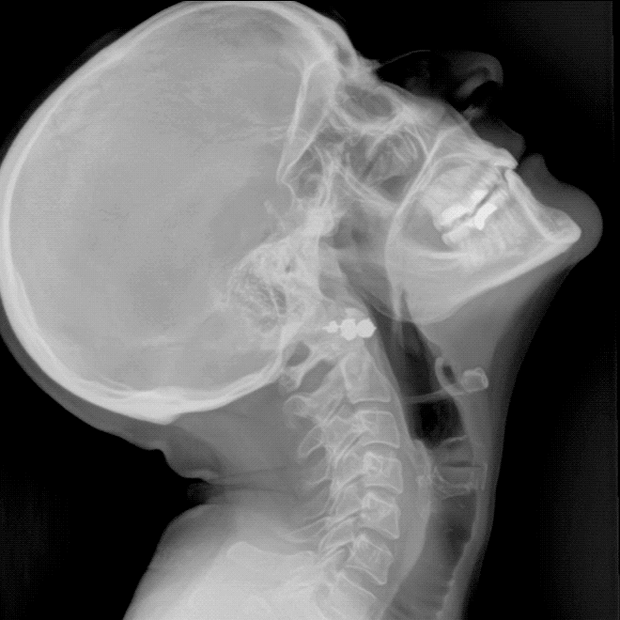

X-Ray Imaging

Premier Mountain Imaging Center is a state-of-the-art facility that specializes in providing high-quality x-ray imaging services. Our team of experienced radiologists and technologists use the latest technology and equipment to produce clear and accurate images for diagnostic purposes. X-ray imaging is a non-invasive procedure that allows us to visualize the internal structures of the body, helping to identify and diagnose a wide range of medical conditions. Whether you need an X-ray for a broken bone or a chest X-ray for respiratory issues, our imaging center is equipped to meet your needs. We prioritize patient comfort and safety, ensuring that each individual receives personalized care and attention throughout the imaging process. Trust Premier Mountain Imaging Center for all your X-ray imaging needs.

We are proud to offer X-ray in motion, also known as Dynamic Digital Radiography. This advanced imaging study must be specifically ordered by a physician. We are the only facility in the White Mountains to provide this exceptional service!